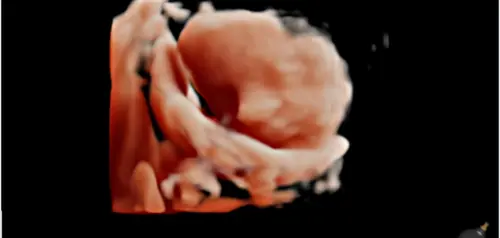

Bij ons lag ze zo lastig dat er maar 1 enigszins normale foto kon worden gemaakt. We mogen maandag voor de herkansing en morgen bij een meisje in opleiding. Dus nog 2 kansen voor hopelijk een beter beeld van onze dochter.